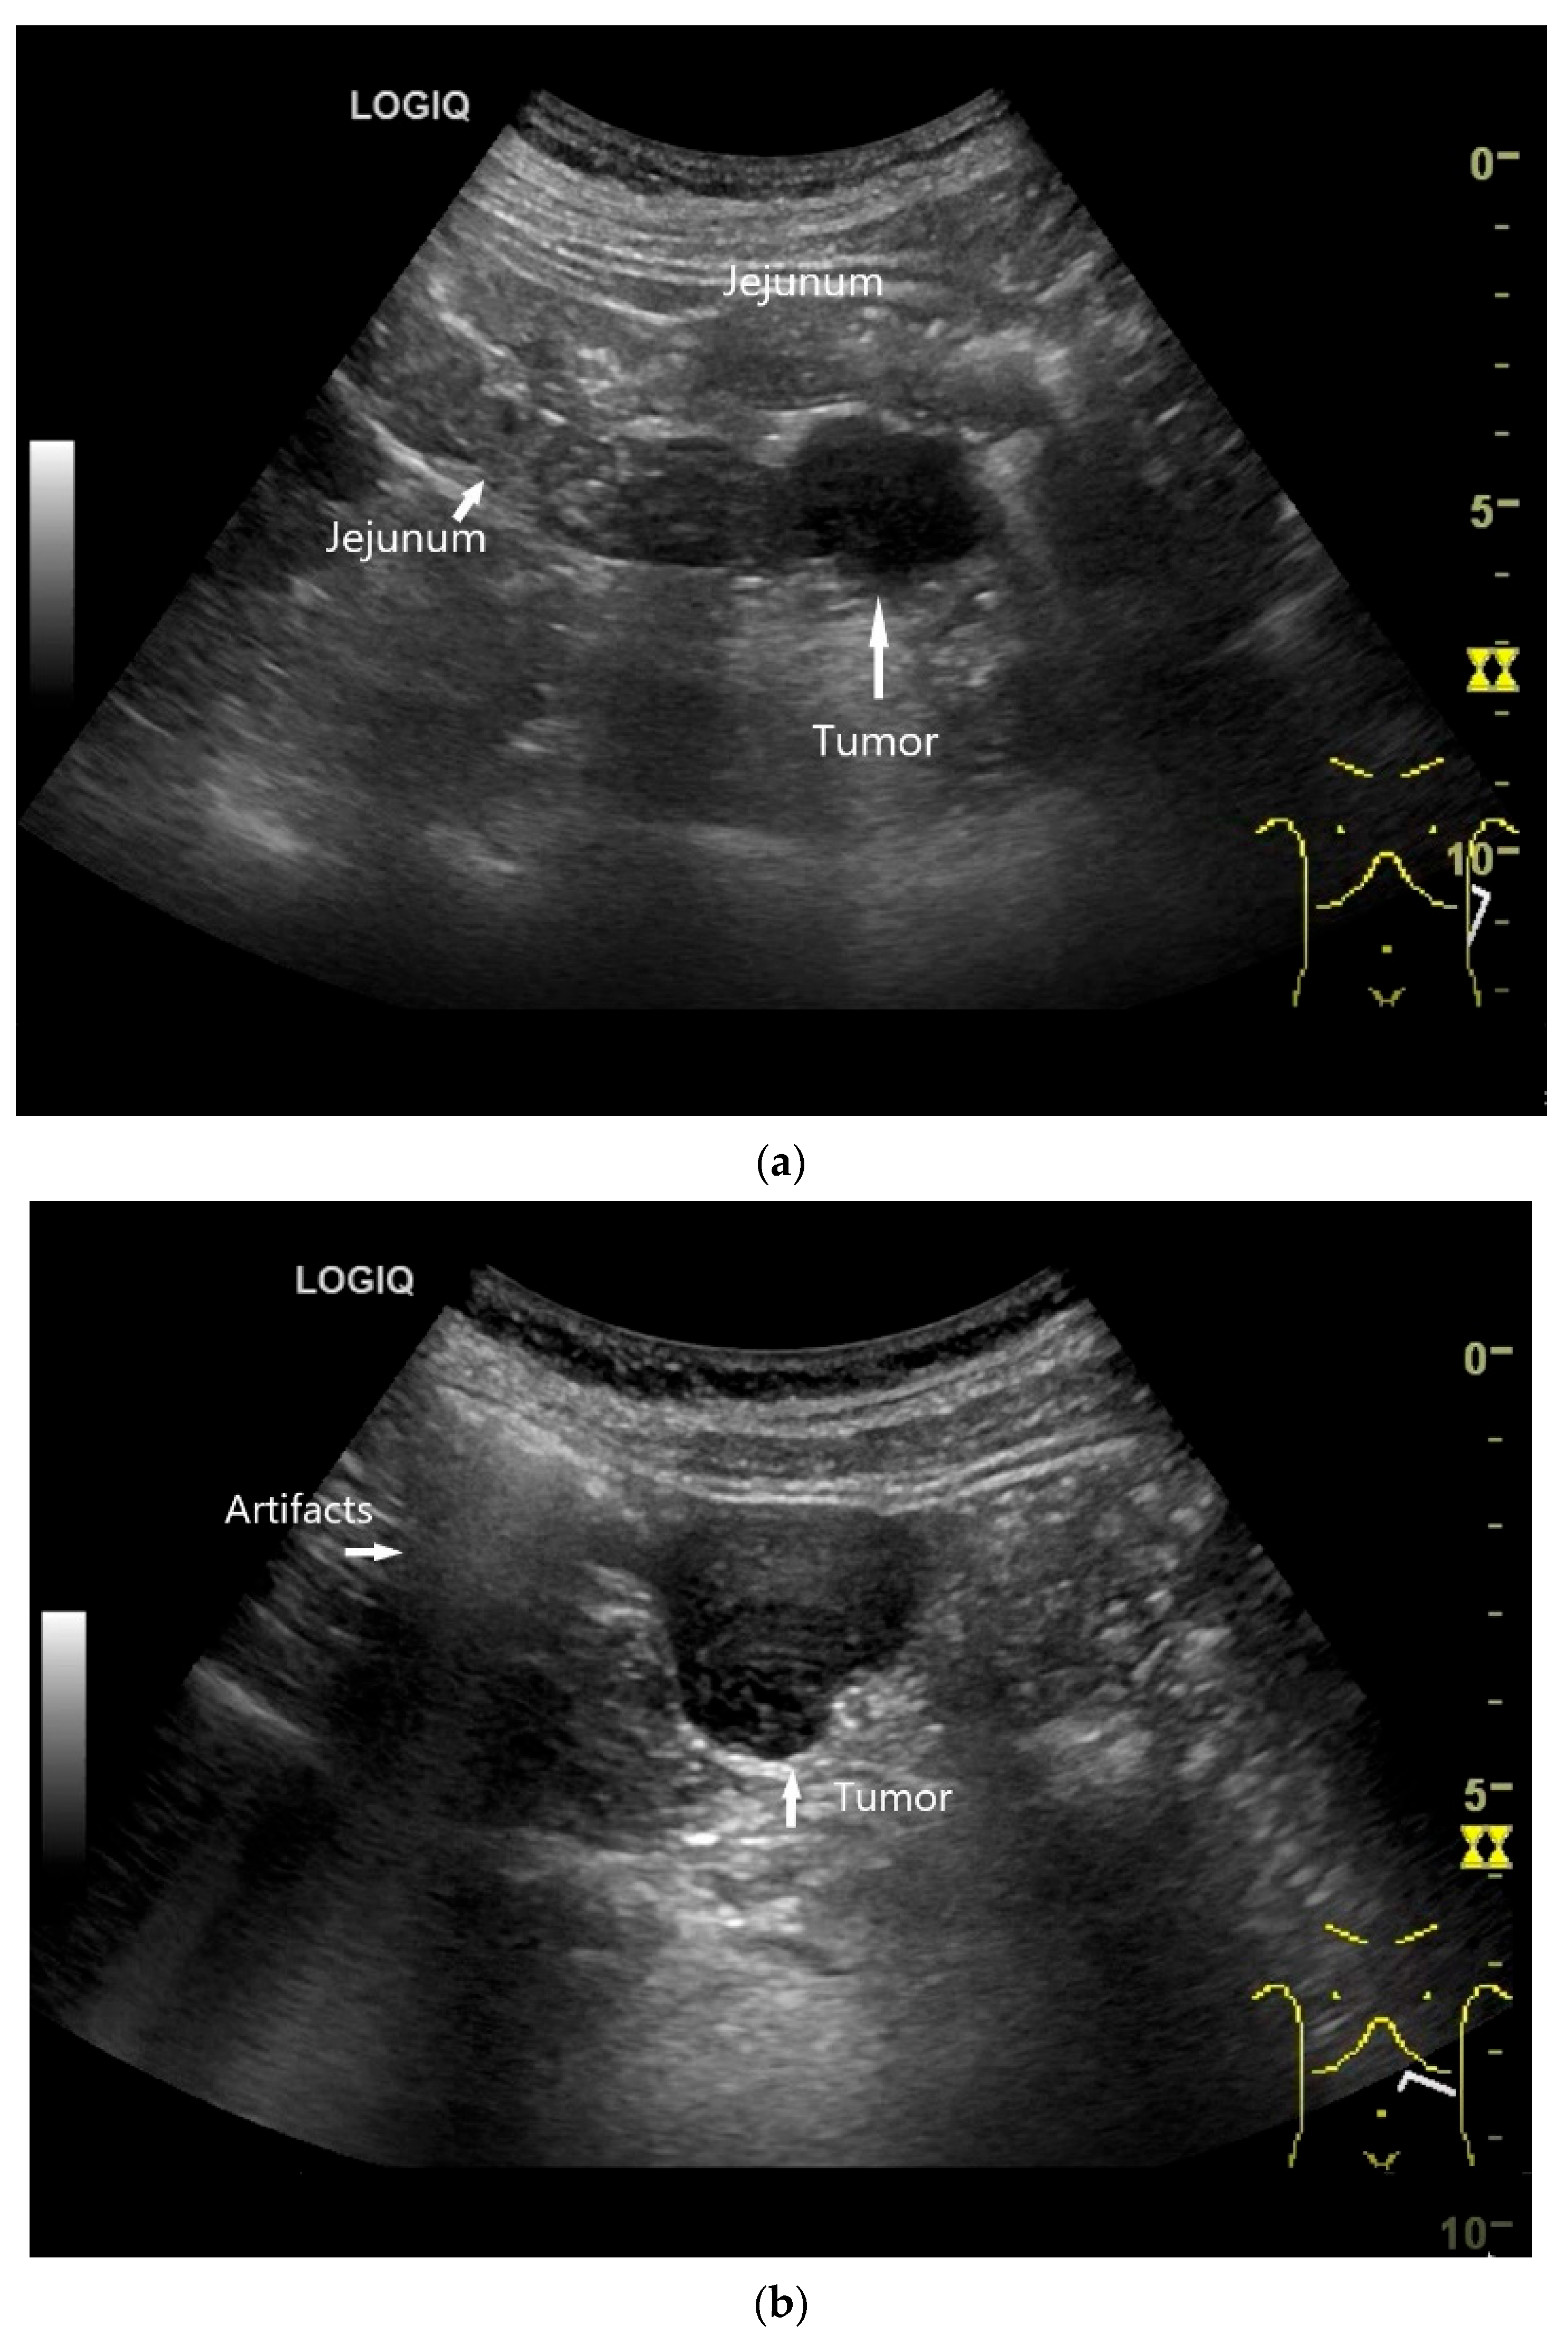

Imaging: Tumors in the jejunum and ileum are usually circular ring-shaped and lumen-stenosing. In the duodenum, about one third have a polypoid component, but a proportion of cases show plaque-like growth [70]. On US, the adenocarcinoma presents as hypoechoic wall thickening with lumen narrowing. The infiltrative wall process may show further tongue-shaped hypoechoic infiltrations into the surrounding tissue. In the case of lymph node involvement, the mesenteric lymph nodes at the level of the tumor may be enlarged and/or morphologically conspicuous [71,72] (Figure 5 and Figure 6).

Figure 5.

Adenocarcinoma in the duodenum. Significant hypoechoic wall thickening (between the markers) with narrowed lumen reflexes (a). The tumor has a slightly polycyclic border on the outside (a,b). Several tumor-suspicious, round, hypoechoic lymph nodes (L) are visible in the paraduodenal region (b).

Figure 6.

Jejunal Adenocarcinoma. Segmental hypoechoic wall thickening (arrows) in the jejunum discovered during anemia diagnostics. Kerckring folds are faintly visible (KF) (a). Adjacent to this is a large round hypoechoic lymph node (L). The surrounding area shows hyperechoic changes (b).